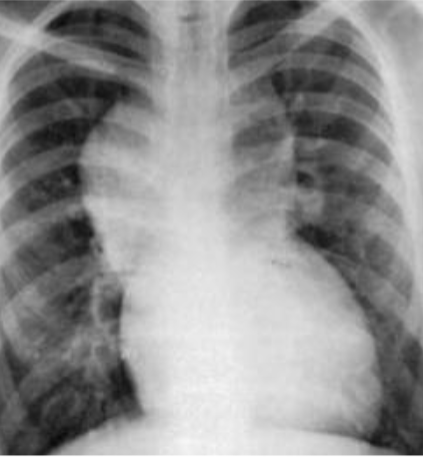

- AP chest film showing moderately increased heart size. Heart diameter to - (1 .trans-thoracic diameter ratio is 78 %. This is a cardiomegaly

- The cause is Congestive Heart Failure [CHF] secondary to viral - (2 .myocarditis